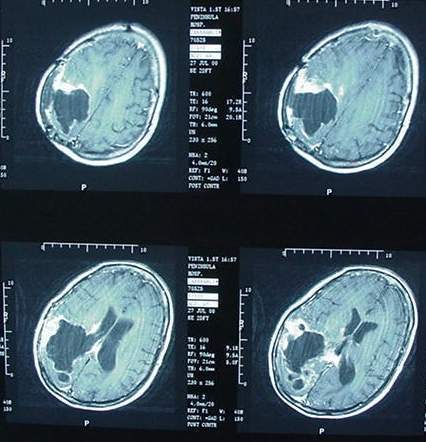

Même si, en général, plus le chiffre d'affaire d'une technologie est élevé, plus il est difficile de démontrer sa toxicité (!), on peut aujourd'hui supposer que la téléphonie mobile, qui n'est donc désormais plus couverte par aucune compagnie de réassurance mondiale, bien qu'il faille souvent plus de 20 ans à un cancer lié principalement à une pollution environnementale pour se déclarer, est un agent responsable de la recrudescence des pathologies du système nerveux central, comme les cancers du cerveau.

Le 31 mai 2011, le Centre international de recherche sur le cancer (Circ) à Lyon, organisme de l'Organisation mondiale de la santé, classait comme "peut-être cancérogène pour l'homme" (2B) les champs électromagnétiques de radiofréquences, autrement dit les ondes émises par les téléphones mobiles, les experts se sont basés sur une étude montrant un risque de gliome accru de 40% chez des "gros" utilisateurs de téléphone portable (30 minutes/ jour en moyenne sur 10 ans).

Evolution des cancers du cerveau au Danemark et en Finlande :

- Augmentation de 40% des tumeurs cérébrales au Danemark de 2001 à 2010 - Registre du Cancer Danois - 16/12/2011

Augmentation de 50% des tumeurs du cerveau chez les enfants au Royaume-Uni en 10 ans + 40% au Danemark, en Finlande - explosion du phénomène en France - 30/05/2012